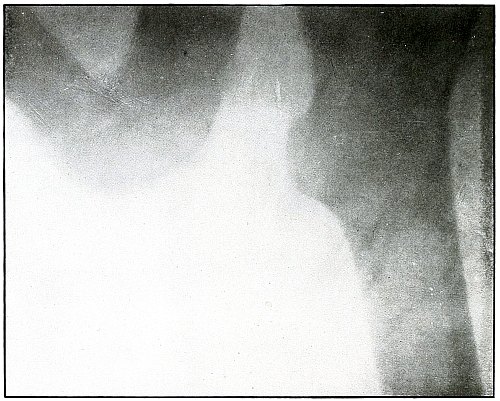

Plate 52.

[Pg 115]

Rifle—Plate 52.

LOWER EXTREMITY.

Gunshot Fracture of the Upper Shaft of the Femur.

The course of the bullet was anteroposterior and pierced the axis

of the shaft of the femur with three radiating lines of fracture,

resulting from the perforating action of the bullet striking the bone

at long range and with greatly reduced energy.

This plate shows the lateral separation of large fragments,

which is typical of gunshot wounds of long range.

Such wounds are usually not infected.

Emergency treatment is antiseptic dressing and coaptation with

extension and temporary splint, so that it may support the bone for

transportation and may be easily removable at place of continued

treatment.

In these cases with lateral separation of fragments, it is imperative

to supplement extension with pressure in a line perpendicular to the

long axis of the femur.

[Pg 116]

Plate 53.

[Pg 117]

Rifle—Plate 53.

UPPER EXTREMITY.

Gunshot Fracture of the Shaft of the Femur

with Lodgment of the Bullet.

The course of the bullet was antero-posterior and diagonally inward

from the antero-external border of upper third of the thigh. A thin

longitudinal fragment was split off without transverse fracture.

The missile struck the thigh after its energy had been greatly

reduced by ricocheting as a result of striking a resisting object

which flattened its nose and “set up” its body, as shown by the wavy

outlines of the shadows.

The dense and normal-size shadow shows the bullet to be near the plate

and probably in the muscles superficially behind and below the lesser

trochanter.

As the prominent outline of the lesser trochanter shows that the

leg was in external rotation when the negative was made, it is

evident that, with the rotation back to the anatomical position, the

projection of the shadow of the bullet would fall close to or in line

with the shaft of the femur; the position of the bullet is behind the

femur.

The treatment is conservative, with no trouble to be expected from infection.